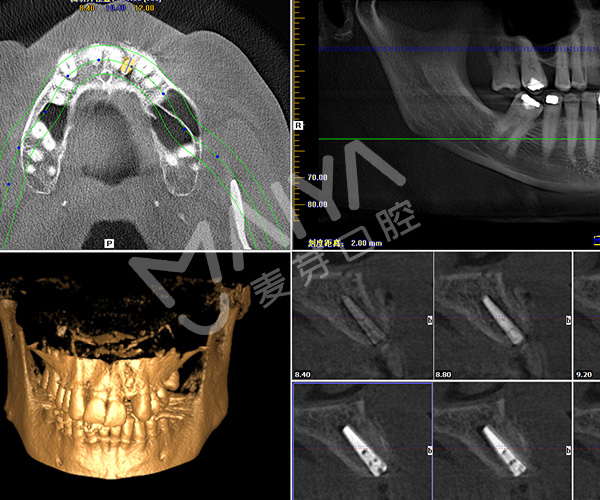

深圳市二院原口腔科主任、深圳麦芽口腔总院长、深圳科技进步一等奖获得者郑苍尚教授在仔细检查Jack的牙齿情况后,通过科学的德国卡瓦数字化口腔CT三维检测,指出Jack因为牙外伤后而导致牙反复发炎松动,牙CT显示牙槽骨严重缺损,不能一期种牙。

3D全景片权威分析

郑院长经过权威分析制定再次种植牙手术的种植方案,首先为Jack拔出患牙做了GPR植骨和保持位点手术,等四个月后缺牙部位形成很好的新骨,再次种牙。

种完牙的口腔全景片